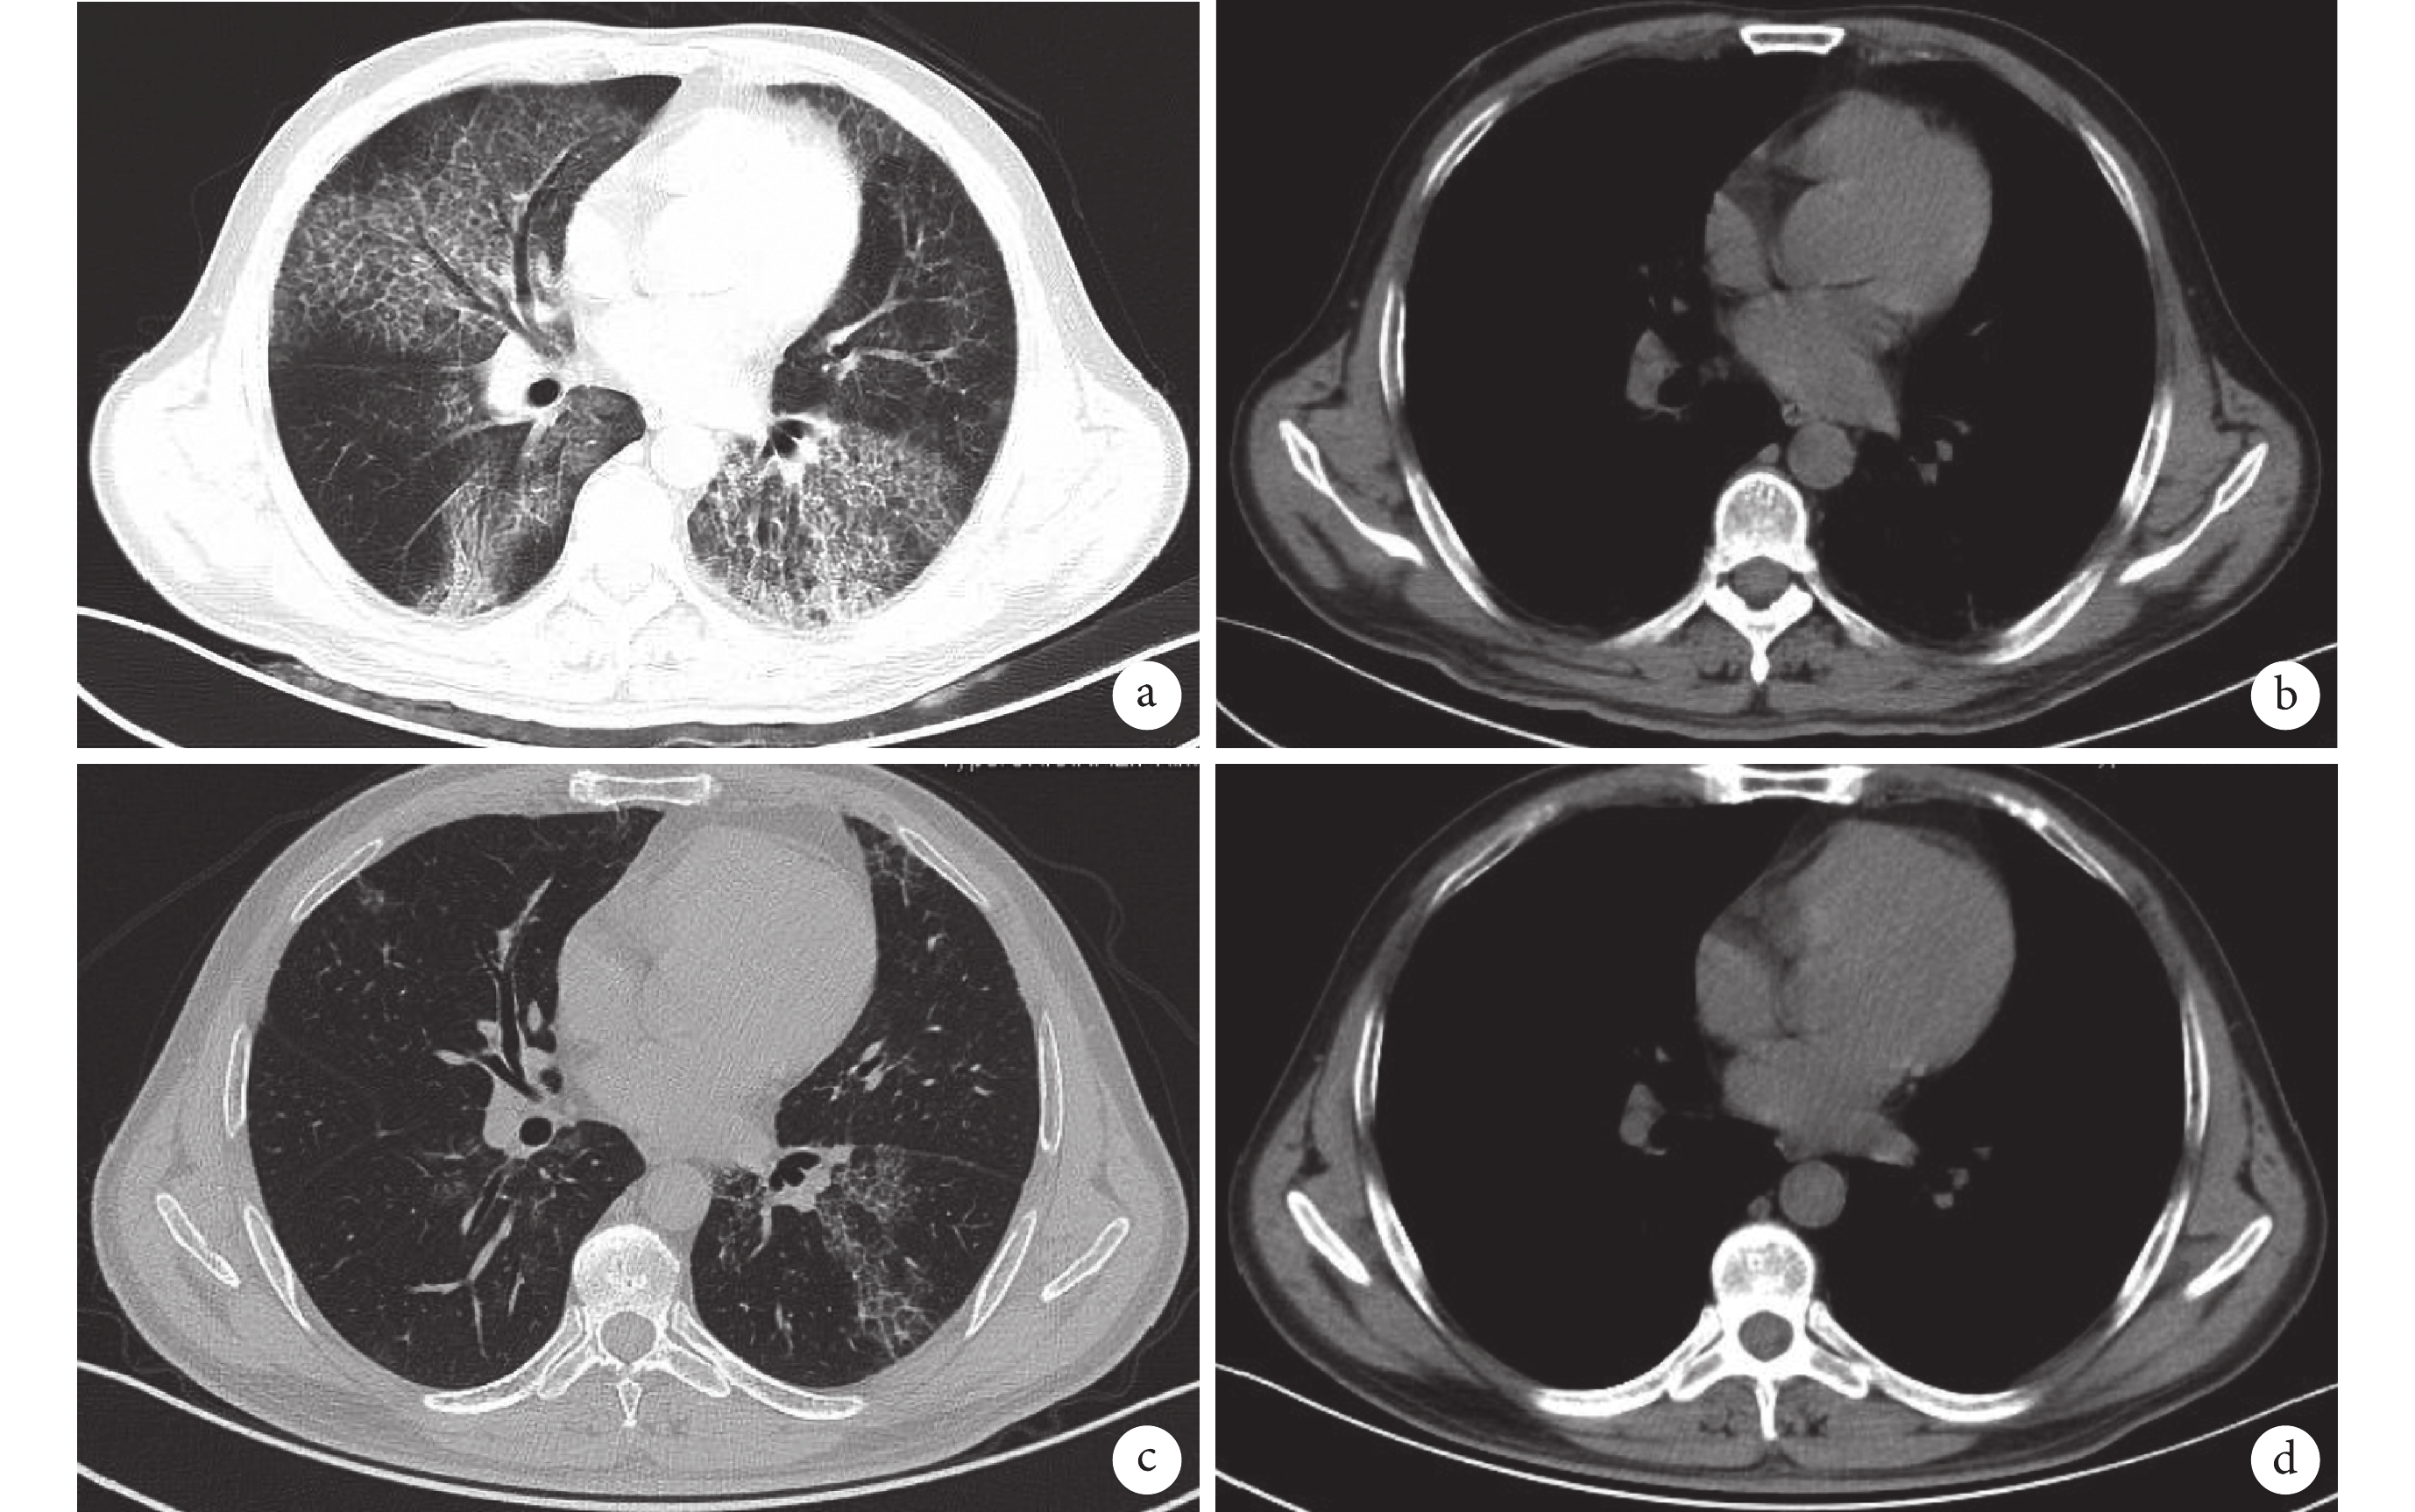

實驗室檢查:2018 年 7 月 6 日血氣分析示 pH 值 7.44,氧分壓 66.8 mm Hg,二氧化碳分壓 31.3 mm Hg;血常規、血生化未見明顯異常;紅細胞沉降率 51 mm/h;降鈣素原 0.22 ng/mL,C 反應蛋白 7.45 mg/L;抗核抗體可疑陽性;免疫球蛋白 E 175 U/mL,類風濕因子 104.0 U/mL;癌胚抗原 9.24 ng/mL,血清癌抗原 15-3 48.92 U/mL,血清癌抗原 19-9 33.30 U/mL,非小細胞肺癌抗原 6.86 ng/mL,烯醇化酶 16.68 ng/mL;輸血前全套、結核 DNA、真菌 G 試驗、曲霉菌免疫學試驗、T 細胞亞群絕對值未見明顯異常。2018 年 7 月 10 日胸部 CT:雙肺透光度降低,雙肺見彌漫斑片影,網格狀影及磨玻璃影,考慮間質性炎癥并間質纖維化(圖1a、1b)。肺泡灌洗液未查見惡性細胞,特殊染色黏卡紅染色(+),抗淀粉酶過碘酸雪夫染色(-)。肺功能示:中度受損。

a. 2018 年 7 月 10 日胸部 CT(肺窗):雙肺彌漫斑片影、網格狀影及磨玻璃影;b. 2018 年 7 月 10 日胸部 CT(縱隔窗):雙肺下葉胸膜增厚,散在結節影;c. 2019 年 1 月 7 日胸部 CT(肺窗):治療 6 個月后雙肺多處病灶明顯吸收;d. 2019 年 1 月 7 日胸部 CT(縱隔窗):治療 6 個月后未見明顯異常

診斷及治療:患者影像學表現符合肺泡蛋白沉積癥(pulmonary alveolar proteinosis,PAP)特點,但肺泡灌洗液抗淀粉酶過碘酸雪夫染色陰性,患者拒絕行肺活檢與全肺灌洗,考慮患者無明顯家族史及繼發疾病,臨床診斷為自身免疫性肺泡蛋白沉積癥(autoimmune pulmonary alveolar proteinosis,APAP),予以粒細胞-巨噬細胞集落刺激因子(granulocyte-macrophage colony stimulating factor,GM-CSF)吸入(150 μg/次,2 次/d,每隔 8 d 用藥 8 d,用藥 3 個月)。3 個月后患者門診隨訪,咳嗽較前好轉,肺功能較前恢復,且無明顯不良反應,第 2 療程調整為 GM-CSF 吸入(225 μg/次,2 次/d,每隔 8 d 用藥 8 d,用藥 3 個月),6 個月后隨訪評估患者癥狀明顯改善,肺功能恢復正常。2019 年 1 月 7 日復查胸部 CT 顯示雙肺多處病灶明顯吸收(圖1c、1d),維持用藥調整為(225 μg/次,2 次/d,每隔 2 周用藥 1 d,用藥 3 個月)。9 個月后隨訪患者咳嗽、咳痰癥狀明顯緩解,經霧化吸入 GM-CSF 后癥狀及影像學表現均好轉,考慮臨床診斷 APAP 成立,繼續 GM-CSF 吸入治療,目前隨訪中。